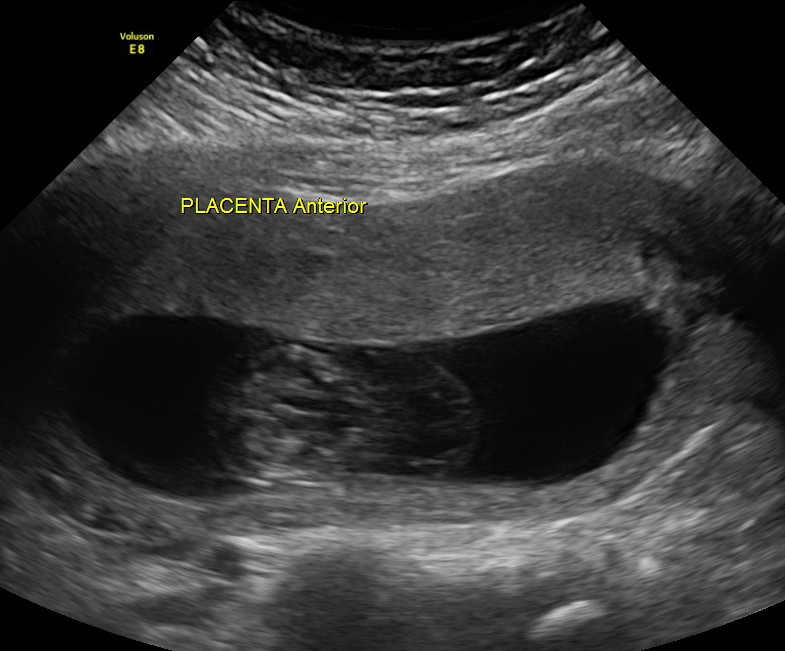

This 23 year old primi gravida, with no history of consanguinity was referred for 2nd opinion for evaluation of cystic swelling of the neck in the first trimester.

The following are the 2 d pictures.

The diagnosis offered was cystic hygroma .